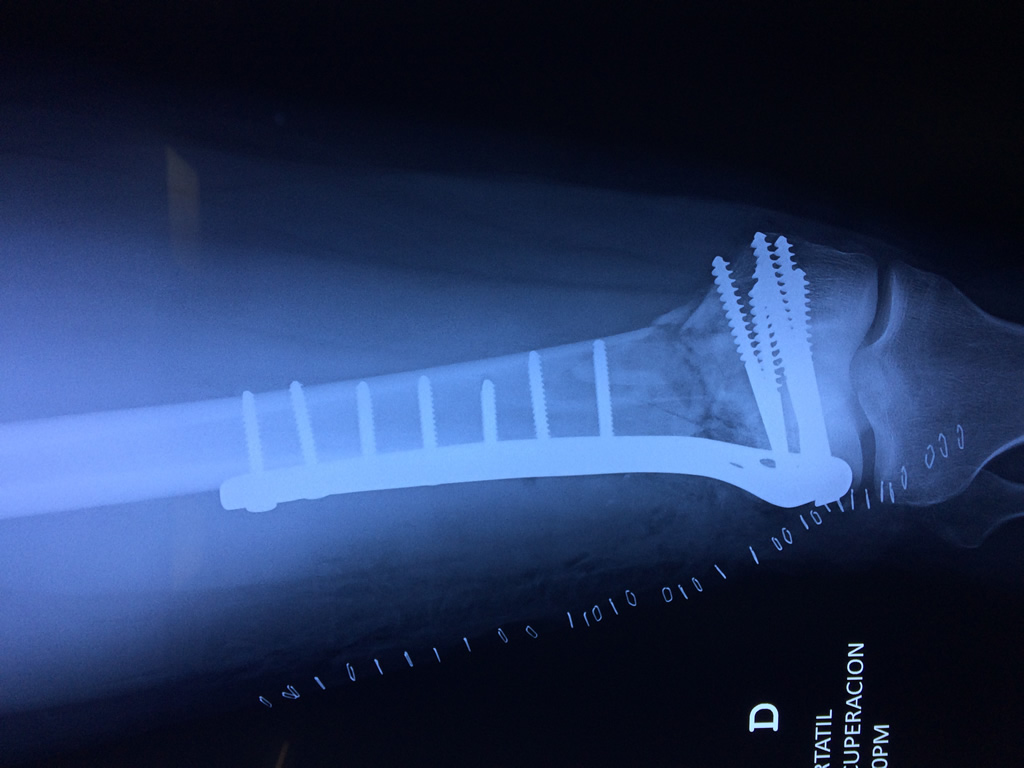

Cirugías de Muñecas